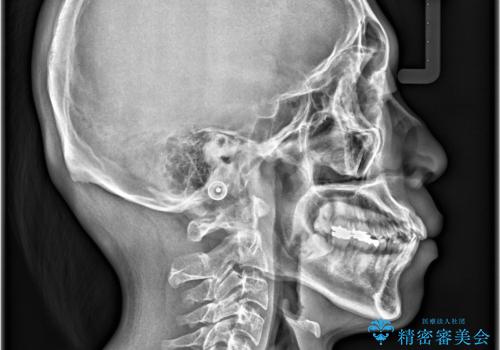

- 「歯のデコボコと前歯が引っ込んでいるのを治したい」を主訴に来院された患者様です。

デコボコの量が多かったため上下左右4を抜歯してワイヤー矯正で治療を行いました。